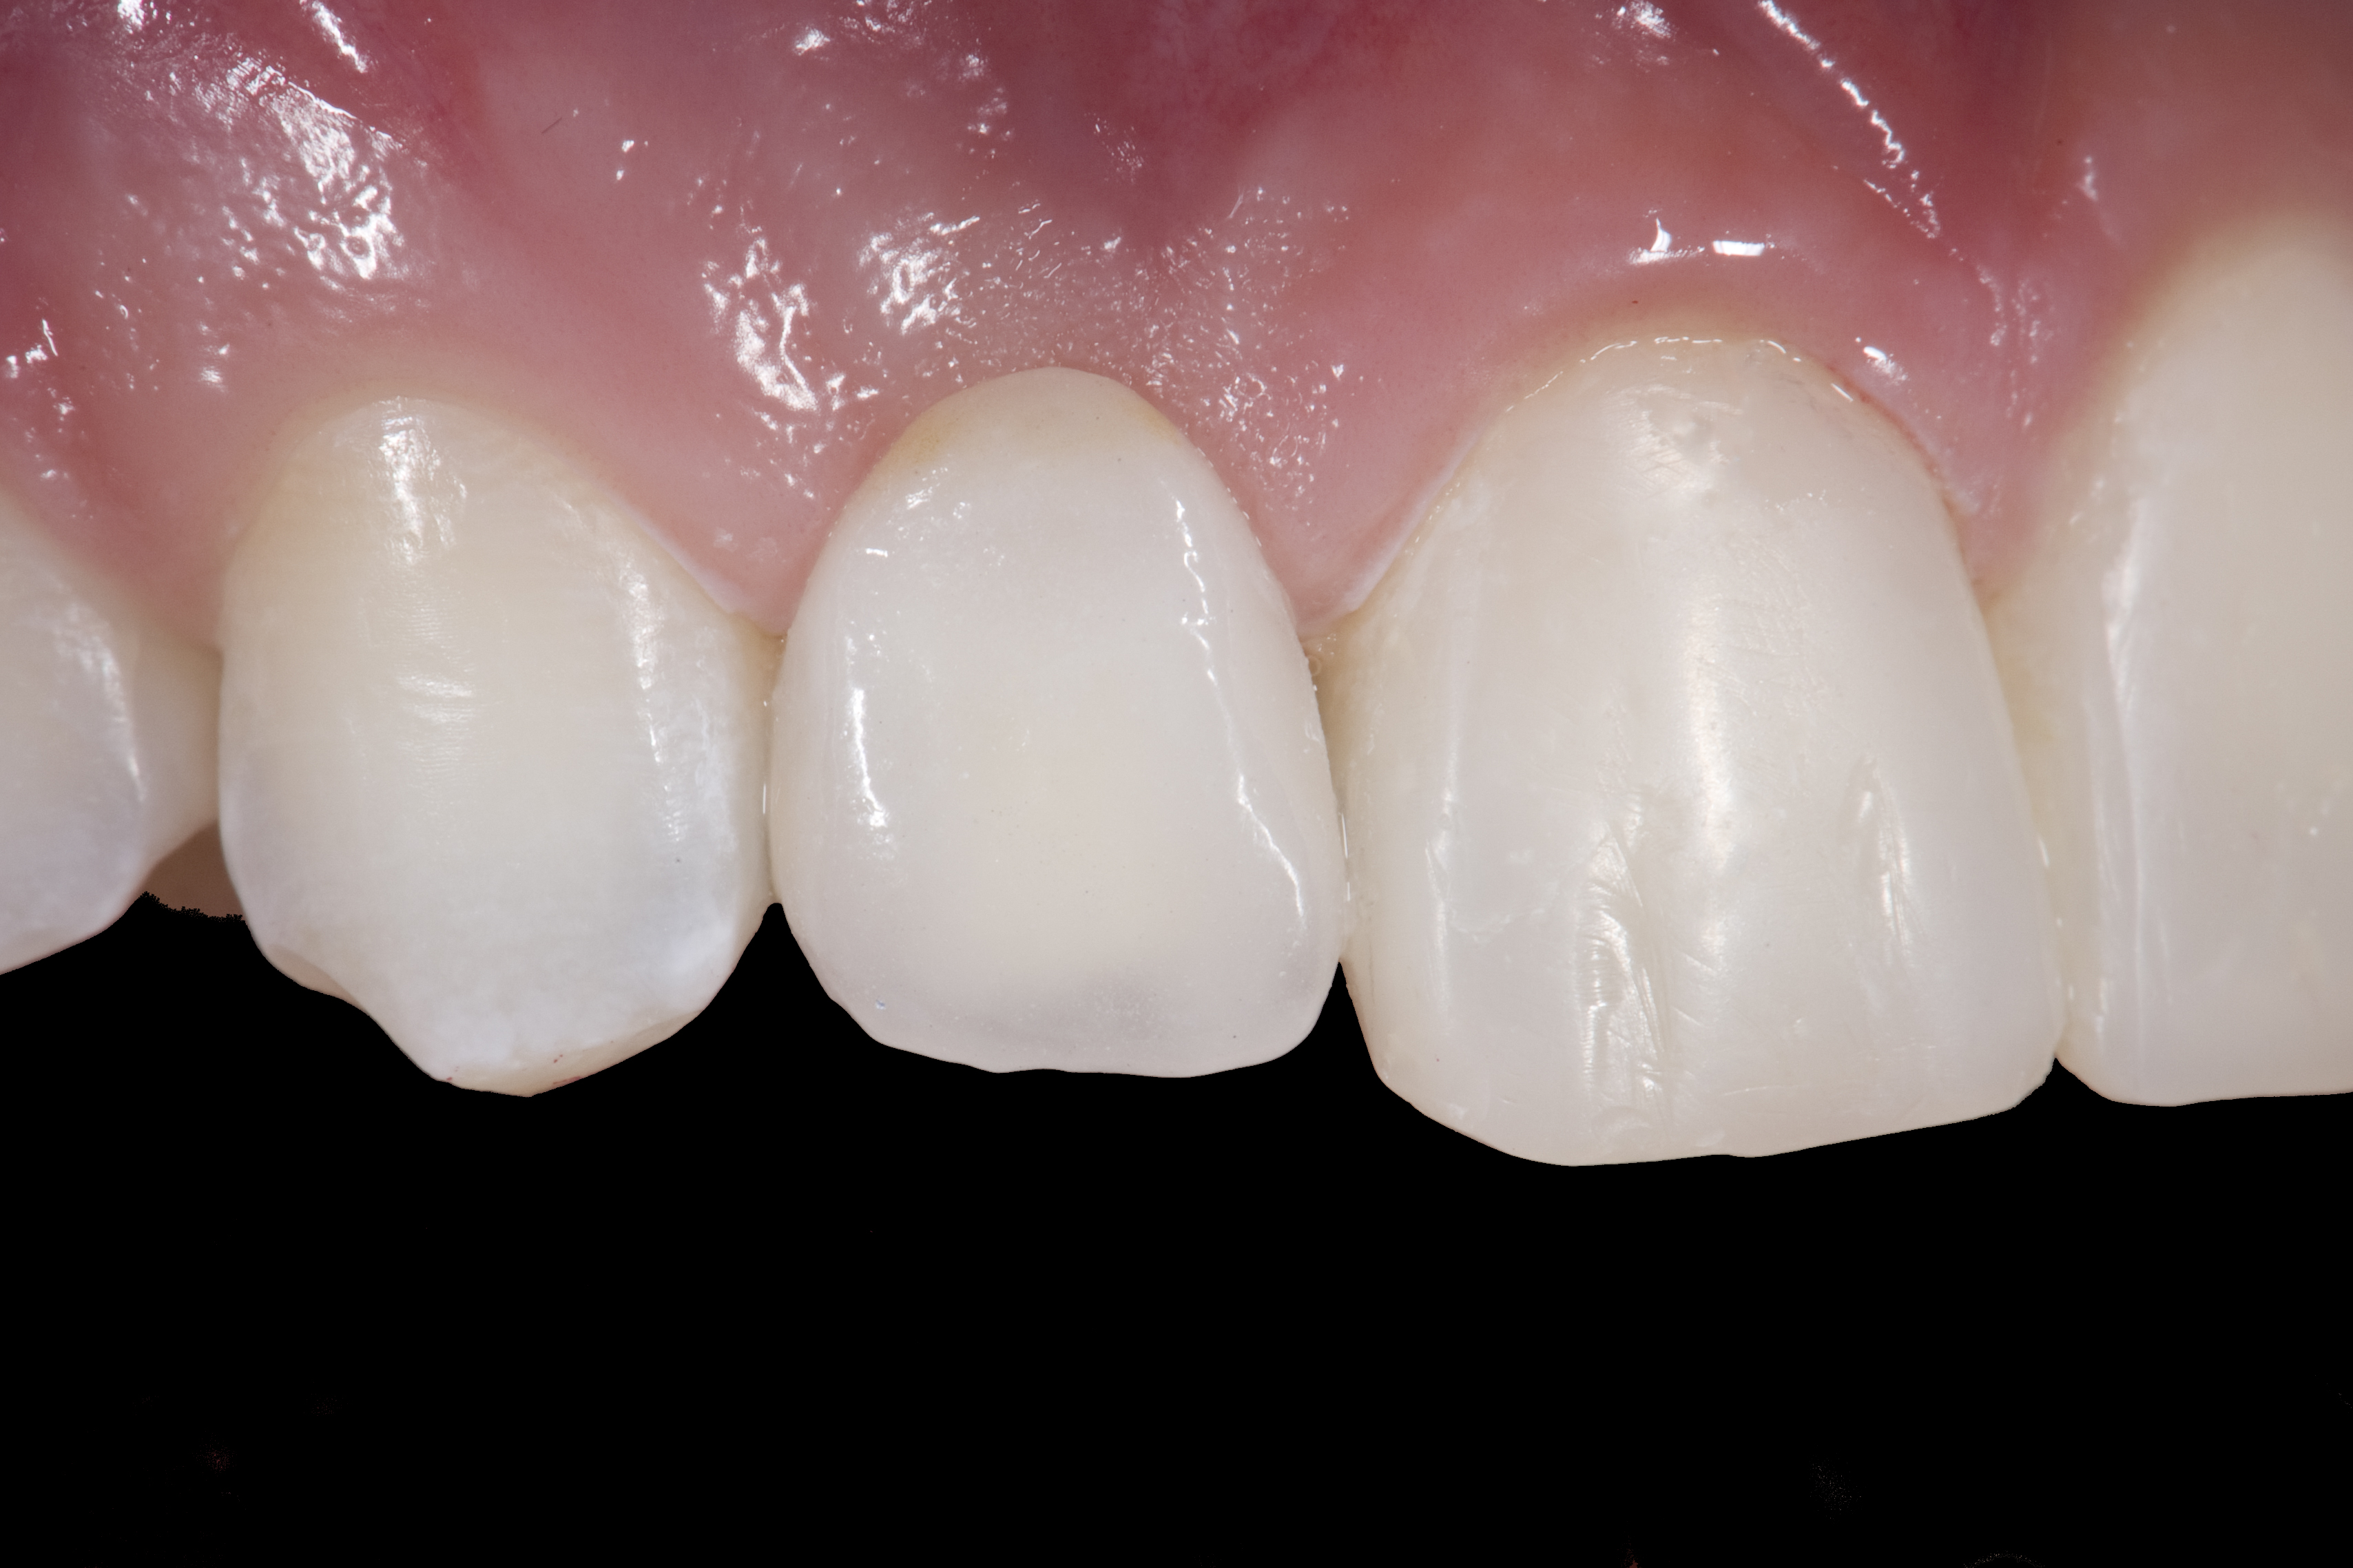

(20.) Facial view of final single-wing, modified zirconia resin-bonded bridges.

Figure 20

When the patient returned, the fit was evaluated in the mouth. Once verified, the internal surface of the framework was etched with a 9.5% hydrofluoric acid for 90 seconds and then salinized. After etching the enamel surface with phosphoric acid for 30 seconds and applying the primer (Single Bond Plus, 3M ESPE) to both the internal surface of the framework and the enamel, the zirconia bridge was bonded with a dual-cure resin cement (RelyX™ ARC, 3M ESPE). After the procedure, the patient ended up with a long-term, high-strength esthetic restoration advantaged by the bonding potential of fledspathic ceramic (Figure 20 through Figure 24). Six years after placement, the prosthesis had remained in place with no complications.